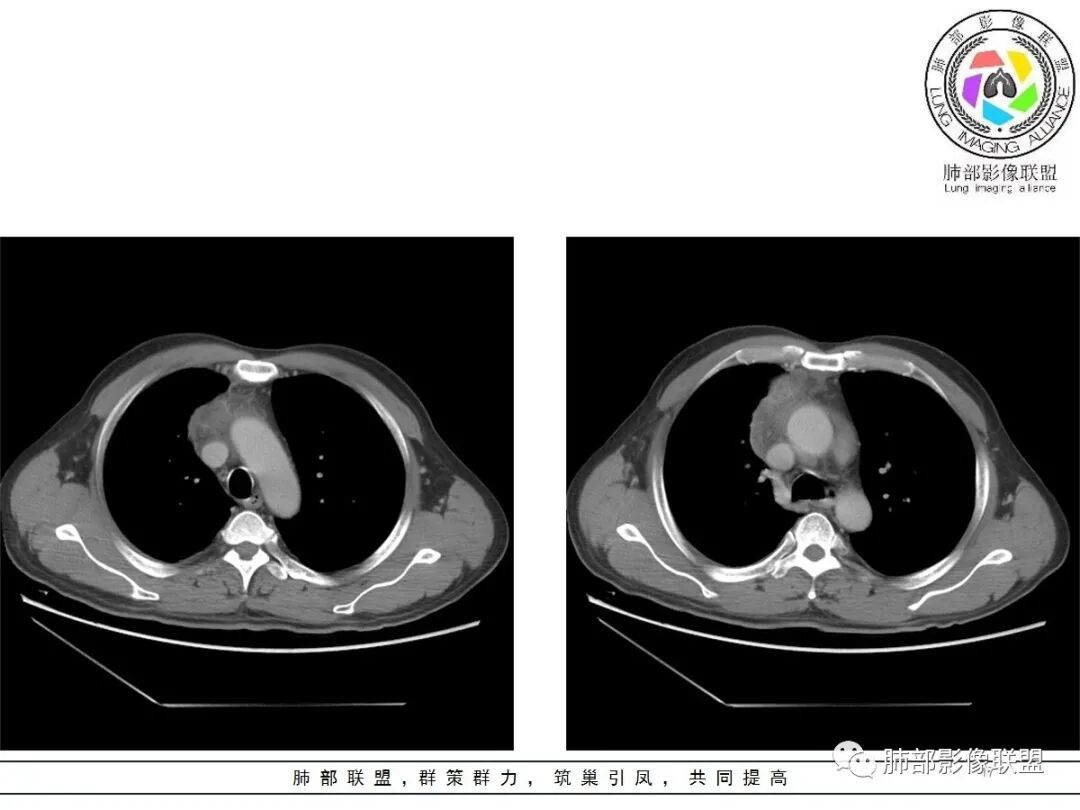

小赵:这个是3月15日的视频

小赵:第二个是3月19日的视频

周围脂肪间隙密度增高,内部小点状很低密度影

右侧少量胸水

19日,4天后, 内部低密度影有,周围渗出增多,胸水增多

2.胸膜掀起,右侧内乳动脉略增粗,定位右前上纵隔内占位。

3.右上纵隔囊实性占位,边界清楚。中央见点状脂肪密度影,边缘见一点状钙化影,增强不均匀环形强化。

4.四天内病灶变化快,块影增大且不规则,包膜似不完整,边界不清,上份可见浸润或渗出,与周围心脏大血管及心包等间隙不清。胸水增多。

第一次的检查符合胸腺瘤影像学改变,短期内的形态学改变及突然出现的边界模糊或浸润等,符合出血或炎症。